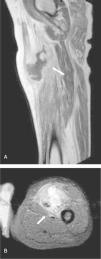

Varón diabético de 35 años con tumefacción espontánea de muslo izquierdo